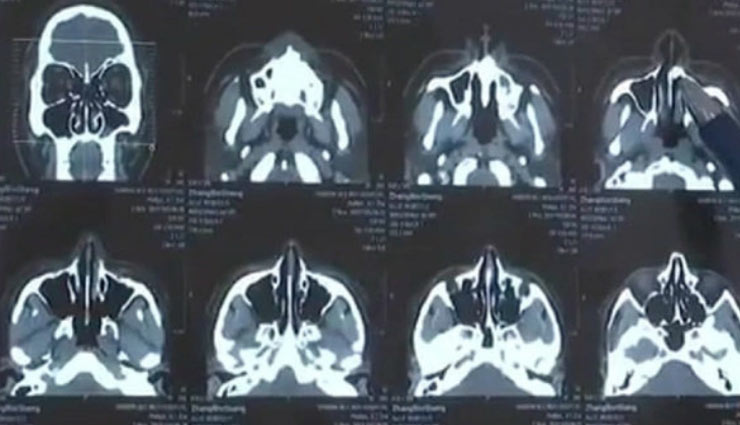

चीन में एक शख्स के नाक में दांत विकसित होने का मामला सामने आया है। 30 साल के झांग बिन्सेंग नाक बंद होने की शिकायत के बाद अस्पताल पहुंचे। जहां डॉक्टर ने एक्सरे करने के बाद बताया कि उसके नथूने में एक सेंटीमीटर का दांत विकसित हो गया है। यह 20 साल से नथूने में है। झांग बिन्सेंग पिछले 3 महीनों से रात में सांस लेने की परेशानी से जूझ रहे थे। उनकी सूंघने की क्षमता भी कम हो रही थी।

दरअसल, 10 साल की उम्र में गिरने से झांग का दांत टूटकर नथूने में चला गया था। वहीं, उसने अपनी जड़ें विकसित कर ली थी। लंबे अंतराल से बढ़ रहा दांत कैविटी का कारण बन गया। डॉक्टर ने 30 मिनट की सर्जरी के बाद दांत को निकाल दिया है। डॉक्टर गुओ लॉन्मेई का कहना है कि जब नाक में दांत गया, तब नाक उसे निकाल नहीं सकी। जैसा वह अंदर आई किसी चीज निकाल देती है।